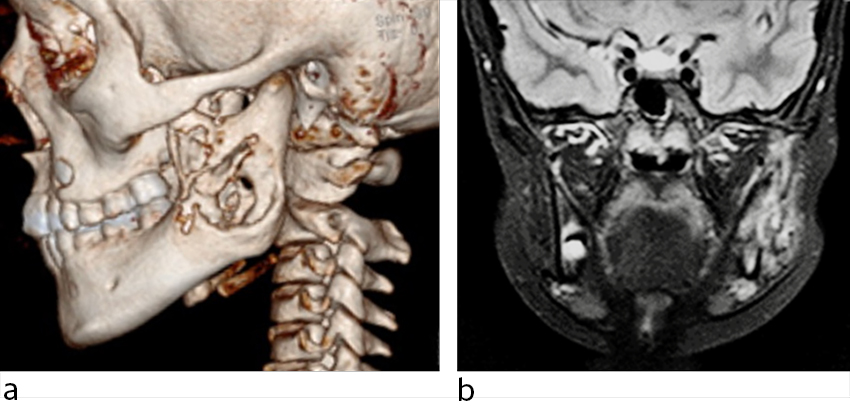

Det ble ikke avdekket tannpatologi ved klinisk undersøkelse, tannrøntgen eller dental panoramarøntgen (ortopantogram, OPG). Antibiotikabehandling med fenoksymetylpenicillin-mikstur 50 mg/mL × 3 (7,5 mL + 7,5 mL + 15 mL) ga tilbakegang av symptomene i løpet av få dager. Nevnte ortopantogram, CT og MR av ansiktsknokler viste omfattende osteolytiske og inflammatoriske lesjoner i venstre underkjeve (figur 1). For å utelukke neoplasi ble det foretatt PET-CT-undersøkelse med fluorodeoksyglukose (FDG), som viste diffust økt FDG-opptak i venstre ramus mandibula.

En jente i barneskolealder ble utredet på grunn av en diffus hevelse over høyre underkjeve. Bortsett fra residiverende ørebetennelser, hadde hun vært frisk. Hevelsen hadde kommet og gått periodevis i et års tid uten ledsagende symptomer. Pasienten hadde ikke hatt feber og var ikke blitt behandlet med antibiotika (figur 2).

Ved klinisk undersøkelse observerte man asymmetri i ansiktet og en fast, lett palpasjonsøm hevelse på ca. 3 cm langs høyre underkjeve uten infeksjonstegn i huden eller tennene. MR- og CT-undersøkelse viste ekspandert ben med ødem i høyre underkjeve og kontrastoppladning i omliggende bløtvev (figur 3).